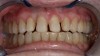

Case Study 2

A 45-year old male patient presented with tooth No. 21 that had an intermediate restorative material (IRM) restoration on the facial aspect after a pulpotomy due to a carious lesion into the pulp from the facial (Figure 7 and Figure 8). The patient had root canal therapy and a post-and-core buildup placed on No. 21 before the crown. The patient was involved in the decision-making for the enamel shade on No. 21. He wanted to make sure that the clinicians did not match No. 21 with No. 20 because he felt the shade on No. 20 was too dark. Instead, the patient wanted to match the new ZLS that had been planned on No. 21 with the natural shade of No. 23 and No. 24. The facial and occlusal views revealed the obvious differences in shade between No. 21 and No. 20. The plan was to use pressable ZLS due to its esthetics, shade-matching abilities, strength, and ease of finishing, so it was decided to involve the dental laboratory technician with the shade-taking process. In planning the discussion with the laboratory technician, the author felt that the best shade would be a Vita A3.5. However, because the laboratory technician worked about 90 minutes away, the author wanted to get his input on the shade by sending him several photographs using the shade the author felt tooth No. 21 was (ie, Vita A3.5) plus shades that were close (ie, Vita A3 and Vita A4). Laboratory technicians are more familiar with shading techniques and may see something that the dentist did not see in the surrounding teeth. This is important when using ZLS to take full advantage of the blending ability that this material displays. The final crown displayed a vibrant match of hue and chroma (Figure 9 through Figure 13).